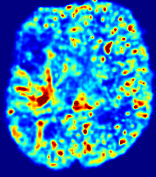

Slice #1Slice #2Slice #3Slice #4Slice #5Slice #6Dgtsuperscript𝐷gtD^{\text{gt}}Refer to captionRefer to captionRefer to captionRefer to captionRefer to captionRefer to caption(a)Refer to captionRefer to captionRefer to captionRefer to captionRefer to captionRefer to caption(b)Refer to captionRefer to captionRefer to captionRefer to captionRefer to captionRefer to caption(c)Refer to captionRefer to captionRefer to captionRefer to captionRefer to captionRefer to caption(d)Refer to captionRefer to captionRefer to captionRefer to captionRefer to captionRefer to caption(e)Refer to captionRefer to captionRefer to captionRefer to captionRefer to captionRefer to caption(f)Refer to captionRefer to captionRefer to captionRefer to captionRefer to captionRefer to captionRefer to caption000.060.060.060.120.120.120.180.180.180.240.240.240.300.300.30(mm2/s)𝑚superscript𝑚2𝑠(mm^{2}/s)

Figure 13: PIANO effectiveness and robustness testing: diffusion imaging via diffusion. Top row shows Dgtsuperscript𝐷gtD^{\text{gt}} used for simulating the ground truth pure diffusion. (a)-(f) refer to the results for D𝐷D estimated from the ground truth pure diffusion image time-series where Rician noise at levels 0%, 2%, 4%, 6%, 8%, 10% was added respectively.

Similarly, starting from the same initial condition C0superscript𝐶0C^{0} as in the ‘Advection Imaging’ experiment for each patient, we simulate concentration time-series {Cti(Ω)|i=0, 1,, 40}conditional-setsuperscript𝐶subscript𝑡𝑖Ω𝑖0140\{C^{t_{i}}\in\mathbb{R}(\Omega)|i=0,\,1,\,\ldots,\,40\} via a diffusion PDE, where we define the ground truth diffusivity D:=Dgtassign𝐷superscript𝐷gtD:=D^{\text{gt}} via the ADC map of the ISLES 2017 training set (ADC values are scaled by 0.000010.000010.00001 to ensure numerical stability):

Note this is likely not a spatially representative ground-truth for perfusion imaging, as it measures different effects from diffusion imaging. However, we still use it as a quasi-realistic pattern of diffusivity in the brain. We also added 2%, 4%, 6%, 8%, 10% levels of Rician noise to obtain simulations of ‘Diffusion Imaging’. The estimated Destsuperscript𝐷estD^{\text{est}} given concentrations of all noise levels for one patient are shown in Fig. 13, PIANO estimation results for all patients are summarized in Fig. 11 (b). Again, PIANO demonstrates its capability to recover the underlying diffusion field. In Fig. 13, when the noise level is increasing, some noisy patterns indeed appear in the associated Destsuperscript𝐷estD^{\text{est}}. Note that the ground truth diffusivity applied in this simulation experiment is about ten times larger than the diffusivity estimated in reality (Fig. 3, Fig. 4).